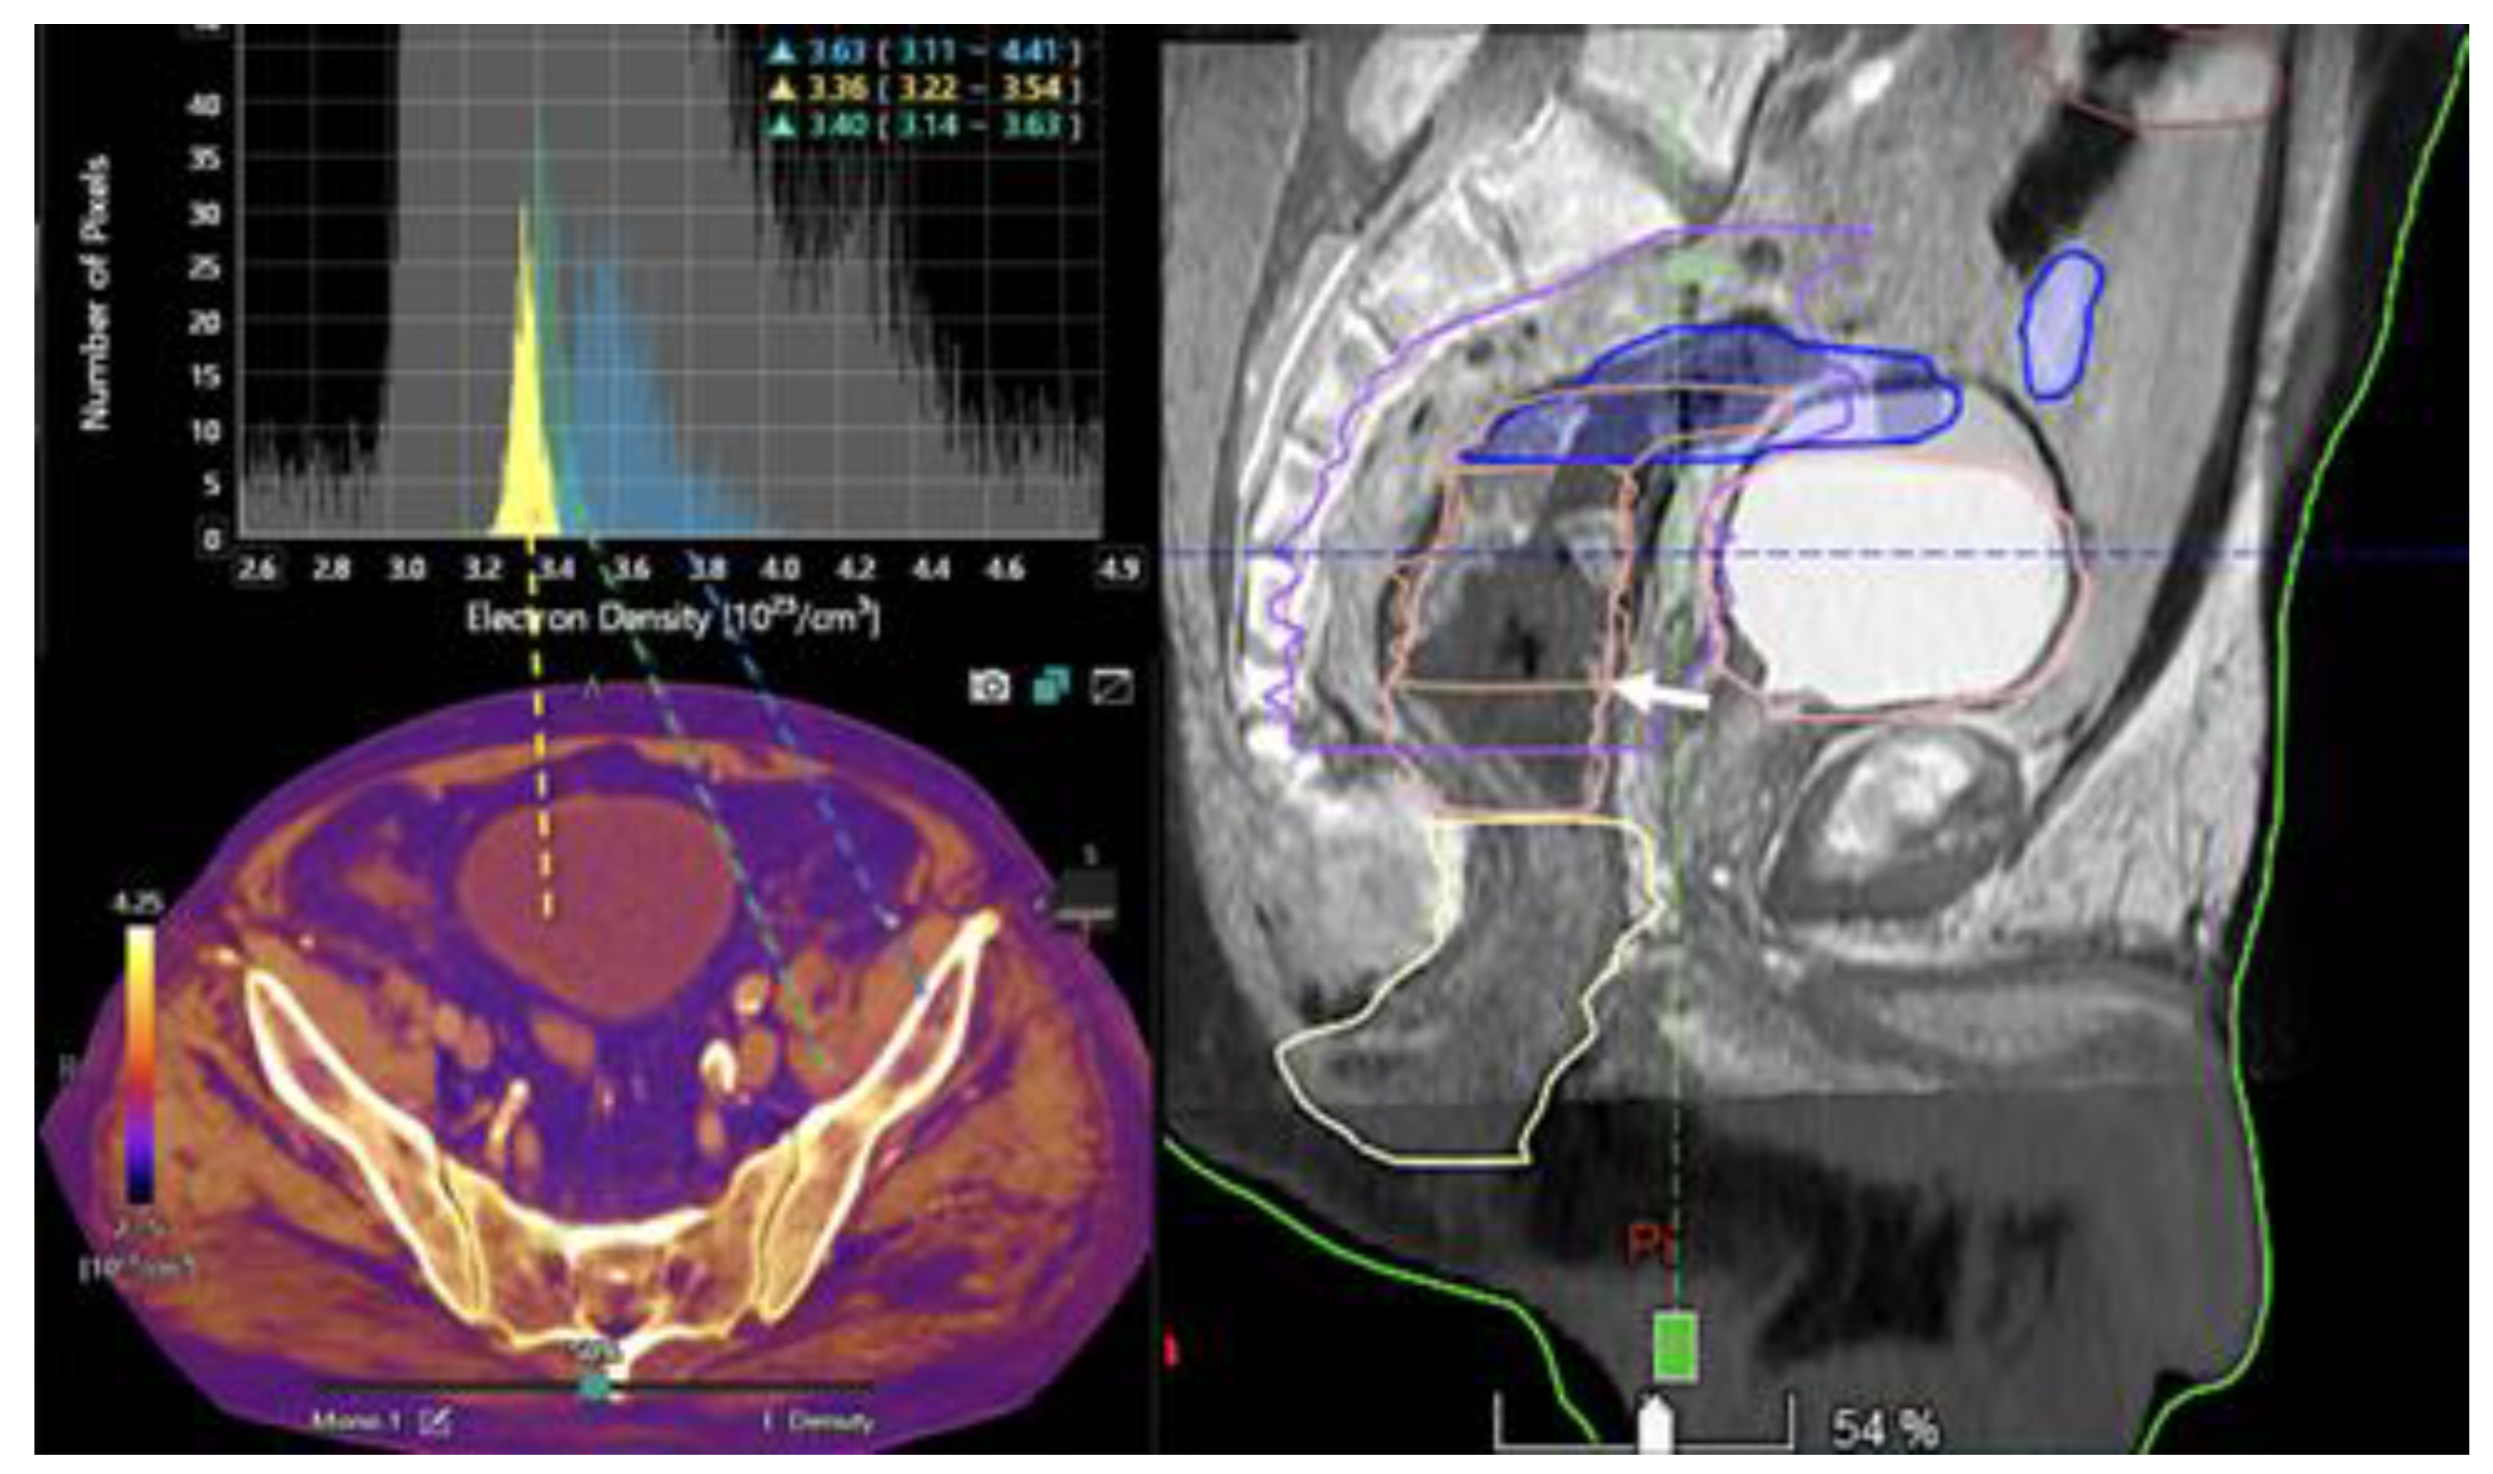

- Kruis, M.F. Improving radiation physics, tumor visualisation, and treatment quantification in radiotherapy with spectral or dual-energy CT. J. Appl. Clin. Med Phys. 2021, 23, e13468. [Google Scholar] [CrossRef] [PubMed]